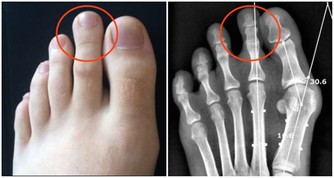

久之這些重金屬就會在腎小管內聚集,嚴重時甚至會引起腎小管的壞死。

我們吃下去之後,這些重金屬就會沉積在我們的腎小管內,久而久之,就會傷及我們的腎臟。

一旦我們再有個高血壓、糖尿病什麼的毛病,腎臟的代償能力會進一步下降。